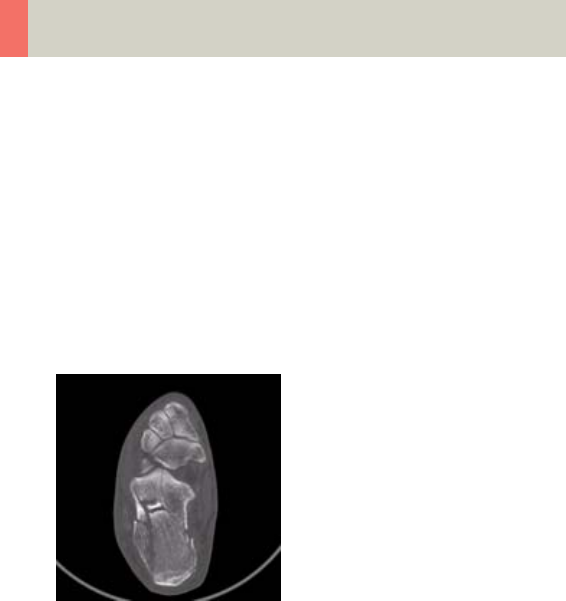

Lower Extremities 346

- Foot 352